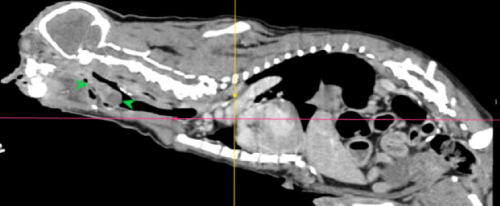

初步懷疑呼吸道阻塞,安排電腦斷層掃描/內視鏡探查手術,精準定位病灶團塊的範圍,

利用內視鏡輔助套環套住團塊後經電燒將可見到範圍盡量切除乾淨。

病理報告為嚴重、慢性活躍性、漿細胞及化膿性喉炎,伴隨肉芽組織生成及局部上皮細胞異型性,會厭旁團塊